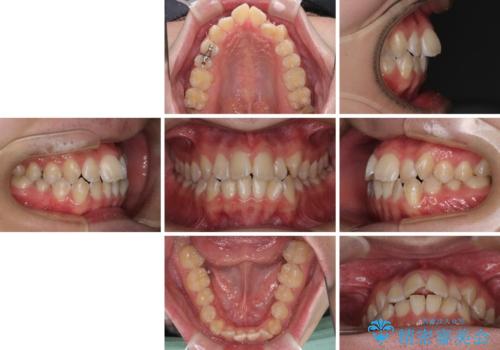

- 上下前歯のデコボコを気にして来院された患者様です。

ワイヤー矯正でもマウスピース矯正でも可能でしたが、短期間で、自身の手を煩わせることなく治療を行いたいとのことで、ワイヤー装置にて矯正治療を行うこととしました。